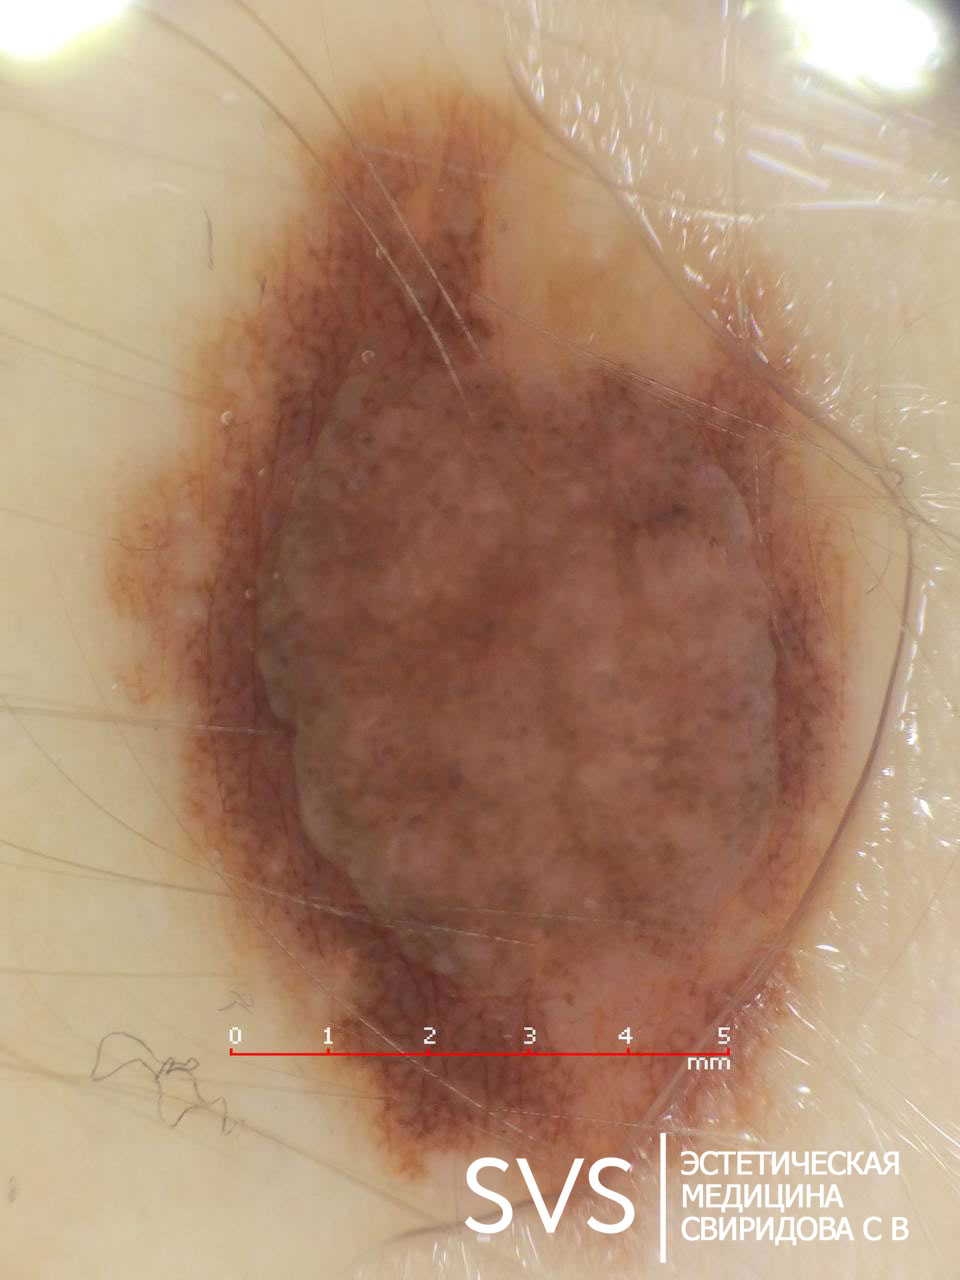

Основным методом инструментального обследования невуса является дерматоскопия. С помощью дерматоскопа врачи нашей клиники получают возможность рассмотреть невус под увеличением.

Это дает возможность выбора правильной тактики лечения новообразования.